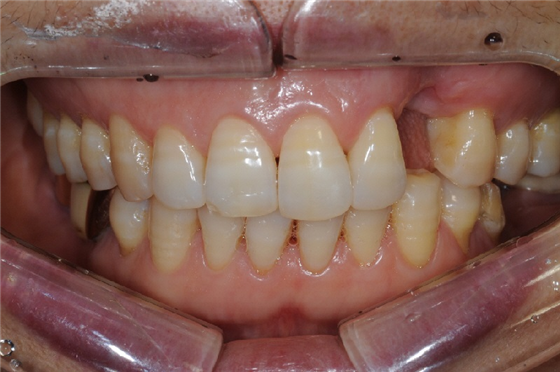

발치 후 2개월이 지났고, 잇몸이 치유되어 임플란트를 안전하게 식립할 수 있었습니다. 전주신시가지치과의 앞니임플란트는 자연스러운 보철물 제작뿐만 아니라, 어금니 보다 더 정교한 처리가 필요합니다.

임플란트의 핵심 요소는 치아가 위치해야 할 영역에 올바른 위치와 깊이에 식립하는 것입니다. 특히 앞니의 경우, 바깥쪽으로 식립되면 잇몸이 높아져 검게 보일 수 있기 때문에 심미적인 측면에서 위치와 깊이가 매우 중요합니다.

수술 전 가이드 핀을 사용해 위치를 설정했습니다. 가이드 핀 없이 픽스처를 심으면 정확한 각도와 방향을 정할 수 없기 때문에 가이드 핀을 활용하면 임플란트 시술의 성공률을 높일 수 있습니다.